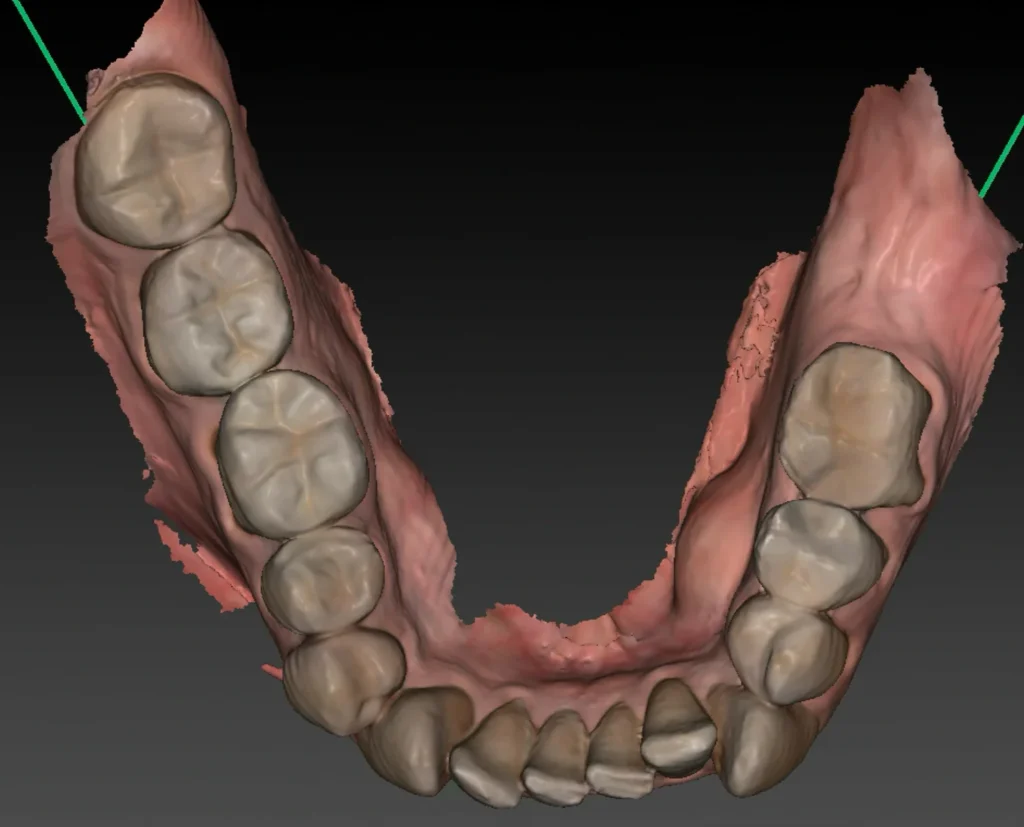

Une fois l’ostéointégration confirmée, la phase prothétique peut débuter. Cette étape consiste à réaliser la ou les couronnes implantaires qui viendront se fixer sur les implants intégrés dans l’os.

La première étape consiste à prendre une empreinte optique ou physique de la zone afin de modéliser avec précision la position de l’implant, la forme de la gencive et l’occlusion. La technique d’empreinte optique, réalisée sans matériau de moulage, est plus confortable pour le patient et permet une transmission numérique directe au laboratoire, accélérant ainsi les délais de fabrication prothétique.

Les données numériques sont ensuite transmises au prothésiste, qui conçoit une prothèse sur-mesure, tant sur le plan fonctionnel qu’esthétique, en tenant compte de la couleur des dents naturelles, de la dynamique occlusale et du projet global du patient.

Une fois la prothèse réalisée, elle est fixée sur l’implant par vissage ou par scellement, selon les indications cliniques. Le résultat final vise à restaurer non seulement la fonction masticatoire, mais aussi l’harmonie du sourire.